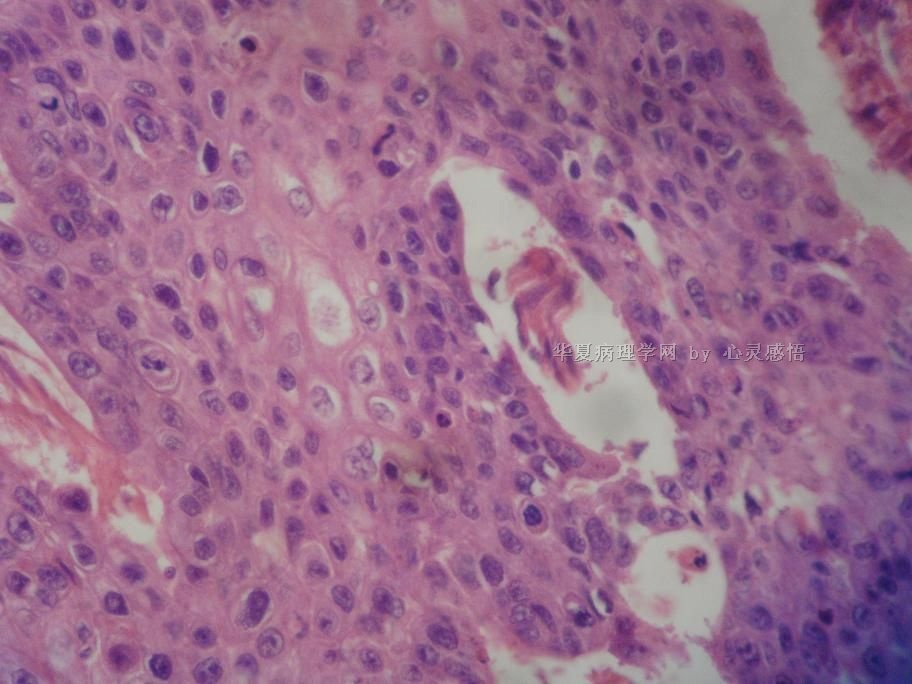

• 食道癌,淋巴结有没有转移,谢谢。图4

图4

1-6图是鳞癌。7-22图片无癌。

淋巴结没有转移

本帖最后由 于 2010-11-17 20:19:00 编辑  图14,19有转移

没有转移。

请教楼主;图片19是淋巴结吗?如果是应该是有癌转移!

没有转移,食道旁的淋巴结和肺旁的淋巴结相似,含有吞噬细胞。